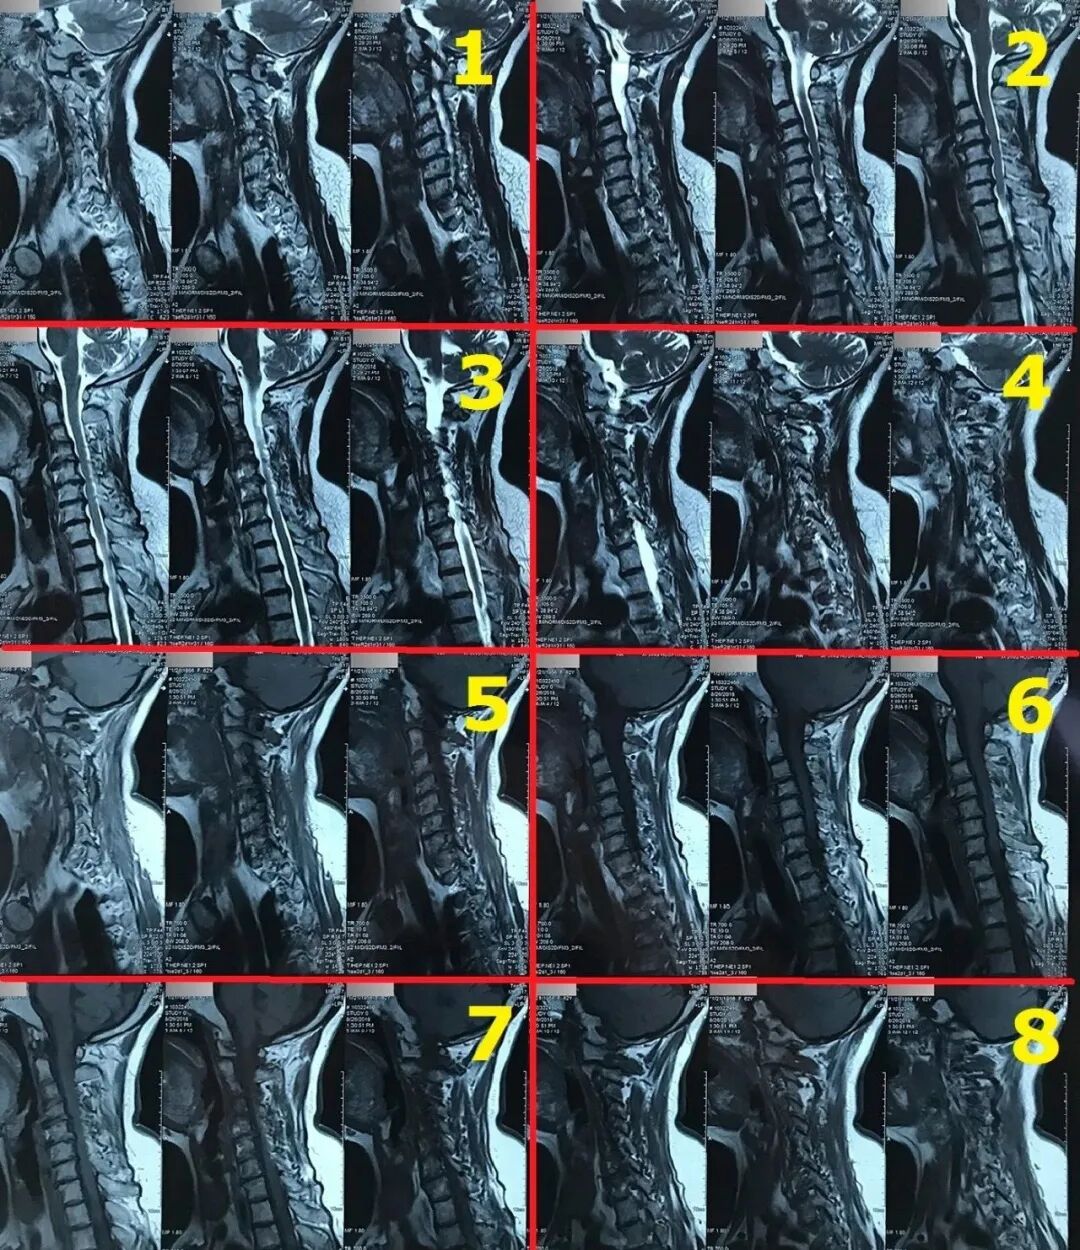

ct打印胶片怎么用远程就医、转院就医时,CT核磁DICOM电子胶片的重要性!【就医知识】_https://www.jmylbn.com_新闻资讯_第1张

(DICOM格式)

ct打印胶片怎么用远程就医、转院就医时,CT核磁DICOM电子胶片的重要性!【就医知识】_https://www.jmylbn.com_新闻资讯_第2张

(JPEG格式)

ct打印胶片怎么用远程就医、转院就医时,CT核磁DICOM电子胶片的重要性!【就医知识】_https://www.jmylbn.com_新闻资讯_第3张

(胶片模式)

DICOM格式电子胶片,可以查看到各个层厚的图像,有些细小病灶,需要通过薄层图像,一点一点去仔细去找到;并且DICOM看片软件,提供了测量功能,可以测量出结节、肿瘤的大小,通过三维成像,还可以看出横截面,冠状位面,矢状位面结节、肿瘤的大小(结节、肿瘤大小是决定结节、肿瘤性质最直观的判定依据)。这些都是打印胶片无法实现的。

如果片子很大,而且一张片子上有很多图像时,就需要将片子分区域,局部放大拍摄了,尽可能将片子上的细节(包括字母等)都拍摄的非常清楚。因为这时还单纯拍一张照片的话,受到手机像素限制,拍出来的照片,放大后,图像就发虚了,医生根本没法看。

将分区的片子,按顺序进行拍摄,即可获取比较有价值的清晰图片。

拍摄时,必须要对着片子上的文字对焦,方向正确,将文字拍摄清晰可视,尽可能多的保留片子上的所有信息。